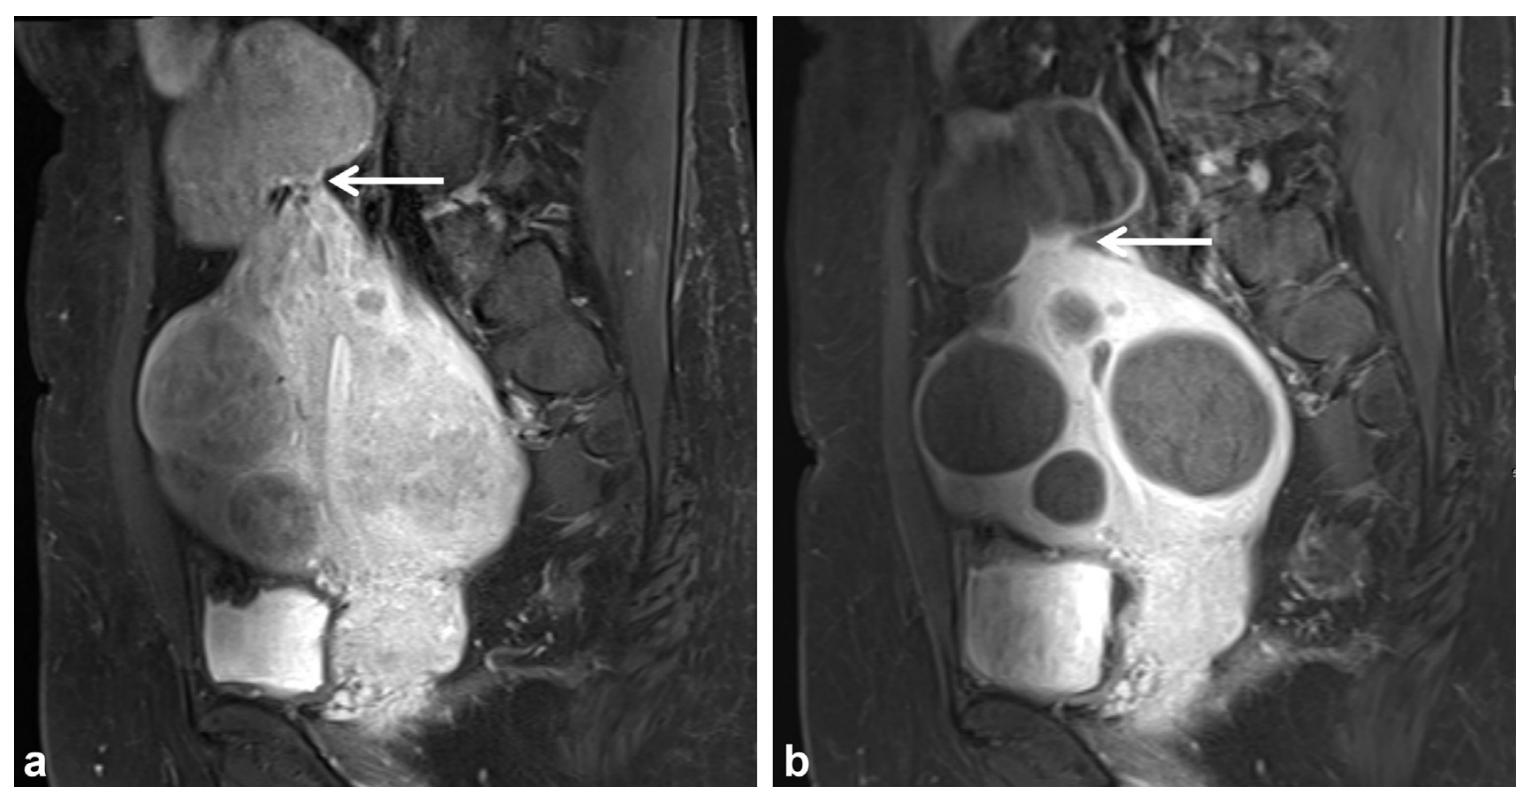

浆膜下带蒂的子宫肌瘤

这部分患者的肌瘤就像树枝挂果子一样,主体是长在子宫体以外的,既往认为这部分子宫肌瘤的患者UAE后可能会造成子宫肌瘤脱落到腹腔。但从临床观察来看,其发生概率极低的,即使肌瘤基底部<25%,坏死脱落至腹腔风险亦无明显增加,坏死率亦无影响,因此浆膜下子宫肌瘤介入治疗是安全、有效的。

浆膜下肌瘤介入栓塞前后MRI对比